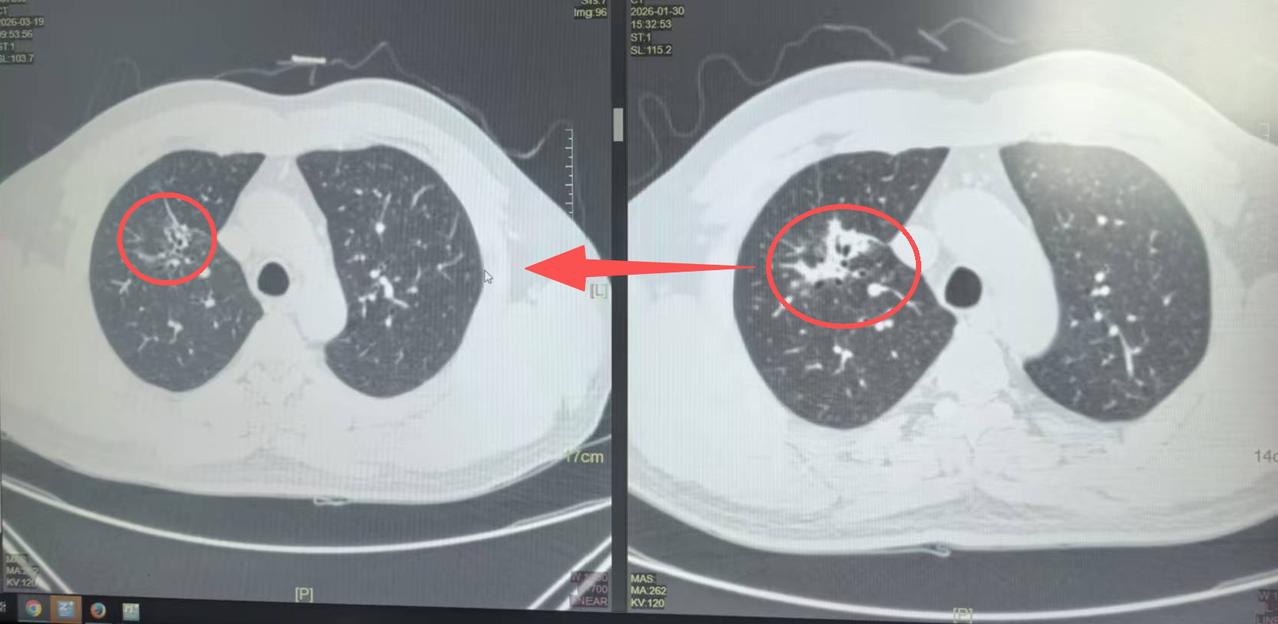

这两位病人都是局部晚期,肿瘤长得特别大,有七八公分,而且还有淋巴结转移——纵隔淋巴结、肺门淋巴结都有,最大的都两三公分。

先经过了3个月的靶向治疗,或者三个疗程的化免,之后我们再给他们安排的手术。

说真的,今天这两个新辅助治疗后的病人,做完手术效果是真的好!肿瘤明显缩小了,淋巴结也消失了,甚至刚刚检测的时候发现,切下来的肿瘤居然全没了,太让人惊喜了。